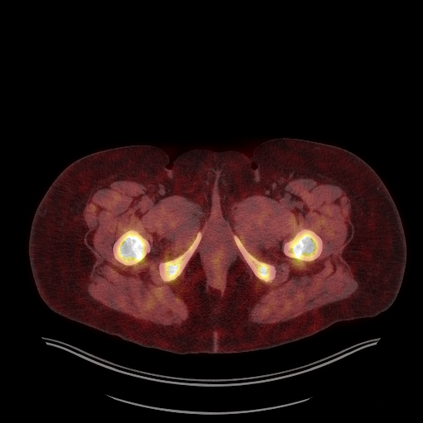

Medical images play a crucial role in assisting diagnosis, remote consultation, and academic research. However, during the transmission and sharing process, they face serious risks of copyright ownership and content tampering. Therefore, protecting medical images is of great importance. As an effective means of image copyright protection, zero-watermarking technology focuses on constructing watermarks without modifying the original carrier by extracting its stable features, which provides an ideal approach for protecting medical images. This paper aims to propose a fragile zero-watermarking model based on dual quaternion matrix decomposition, which utilizes the operational relationship between the standard part and the dual part of dual quaternions to correlate the original carrier image with the watermark image, and generates zero-watermarking information based on the characteristics of dual quaternion matrix decomposition, ultimately achieving copyright protection and content tampering detection for medical images.